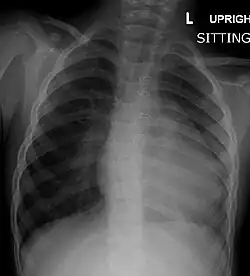

A chest X-ray of a child with tetralogy of Fallot

Before more sophisticated techniques became available, chest X-ray was the definitive method of diagnosis. The abnormal "coeur-en-sabot" (boot-like) appearance of a heart with tetralogy of Fallot is classically visible via chest X-ray, although most infants with tetralogy may not show this finding.[50] The boot like shape is due to the right ventricular hypertrophy present in TOF. Lung fields are often dark (absence of interstitial lung markings) due to decreased pulmonary blood flow.[51]: 171–172

Right ventricular hypertrophy The right ventricle is more muscular than normal, causing a characteristic boot-shaped (coeur-en-sabot) appearance as seen by chest X-ray. Due to the misarrangement of the external ventricular septum, the right ventricular wall increases in size to deal with the increased obstruction to the right outflow tract. This feature is now generally agreed to be a secondary anomaly, as the level of hypertrophy tends to increase with age.[45]